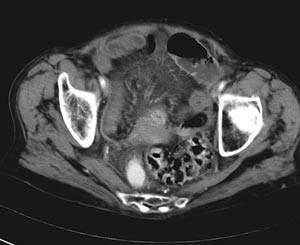

I motsetning til røntgen oversikt abdomen viste abdominal CT multiple luftvæskespeil i tynntarmen. Tynntarmslyngene var til dels moderat utspilte med diameter på om lag 3 cm (fig 1). Bak cøkum kunne man følge en slynge som ble innsnevret i forløpet, som ved obstruksjon. I tynntarmens videre forløp så man veggfortykkelse, økt kontrastoppladning i mukosa og halotegn. Mesenteriet viste stuvning og påfallende konvergens med antydet rotasjon som en virvel (whirl-sign, (fig 2, fig 3).

Funnet var forenlig med strangulasjonsileus, og indikasjonen for operativ behandling var nå åpenbar.